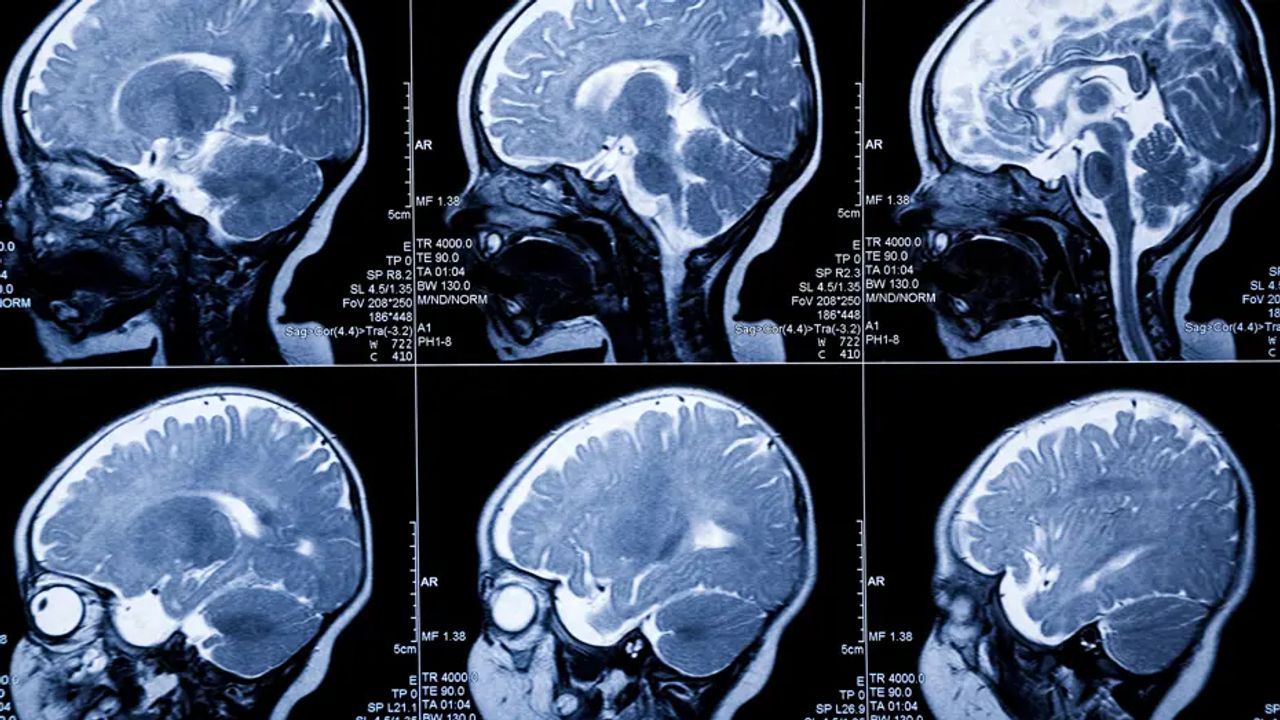

İngiltere'nin Cambridge Üniversitesi uzmanları, yenidoğanların beyinlerini yüksek hassasiyetle görüntülemek için yeni bir teknoloji geliştirdi.

“FUSION” adı verilen teknoloji sayesinde yenidoğanlarda oluşması muhtemel beyin hasarı erkenden tespit edilebilecek.